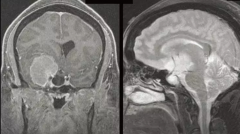

毛细胞星形细胞瘤 是一种生长缓慢、边界较清的囊性星形肿瘤,是一种 良性胶质瘤 病理分型,WHO I级。 发病特点 毛细胞星形细胞瘤常发生于儿童和年轻人...

小儿丘脑肿瘤常被认为是无法手术的。但是,现代显微外科技术以及神经影像学的改进使得能够进行准确的术前计划,可以以更顺利的方式进行切除...